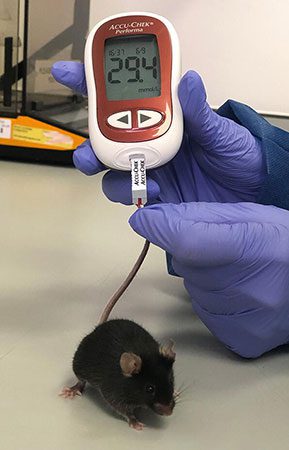

- Blood sampling from the heart, tail vein, jugular vein and ocular sinus

- Create and induce a variety of animal models